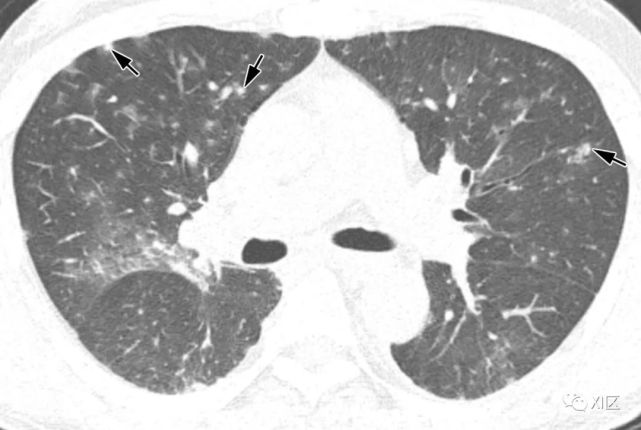

图片

图14 一位22岁女性感染前1个月因急性淋巴细胞白血病接受单倍体相合骨髓移植治疗,有发热,诊断为 HPIV病毒性肺炎。

在主支气管水平(上)和叶间区水平(中上)的初始轴位胸部CT图像显示沿支气管血管束和轻度支气管壁增厚(箭头)的多灶性不明确结节性GGO病变(箭)。中性粒细胞减少持续存在。(中下,下)随访10天后获得的轴位胸部CT图像显示病变的范围和强度增加,并沿支气管血管束增加不规则的实变结节(箭)。尽管进行了重症监护,该患者仍然死亡。